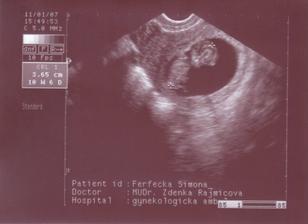

SRPŇÁTKA 2007 - fotky UTZ

album věnované mimískům, které se narodí v srpnu 2007 a jejich maminkám ze "Společného termínu SRPEN"